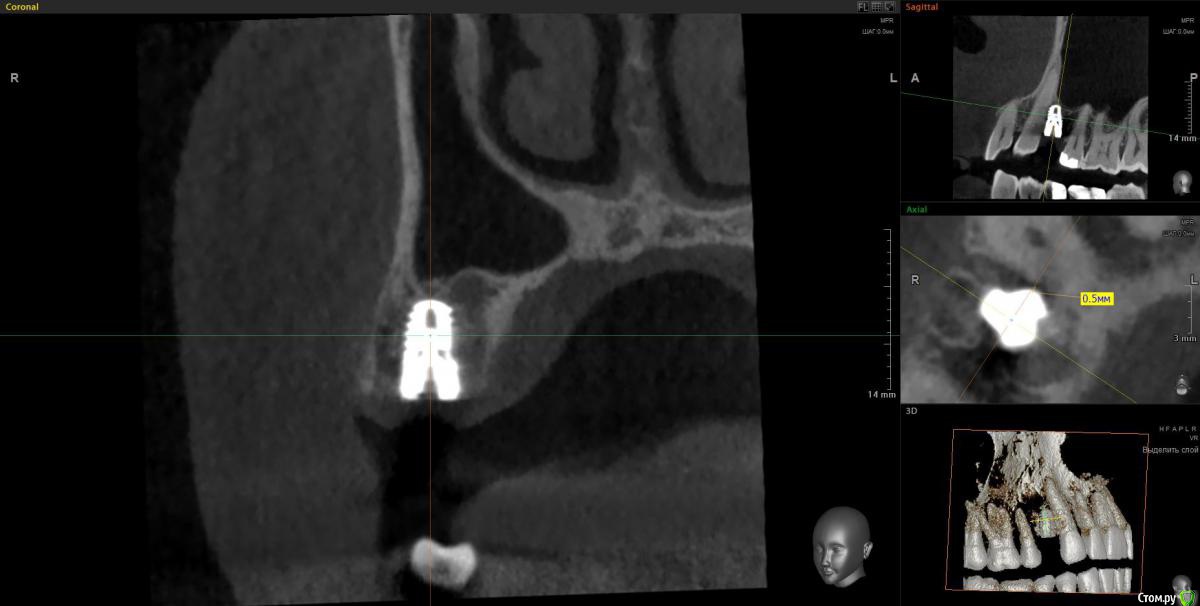

Doctor Vlad Опубликовано 14 апреля, 2020 Поделиться Опубликовано 14 апреля, 2020 Вчера одномоментно. кт только сегодня. Жалоб нет. Хотя там и сст с неба. конечно клык не сверленый, но близость напрягает. Съехал он при установке. Поленился снимок делать после установки, ушил лунку с трансплантатом, во рту норм выглядел. А потом на рг не очень) контроль кт Оставить? убрать недели через 3? Ссылка на комментарий

It'sGeorgy Опубликовано 14 апреля, 2020 Поделиться Опубликовано 14 апреля, 2020 Вчера одномоментно. кт только сегодня. Жалоб нет. Хотя там и сст с неба. конечно клык не сверленый, но близость напрягает. Съехал он при установке. Поленился снимок делать после установки, ушил лунку с трансплантатом, во рту норм выглядел. А потом на рг не очень) контроль кт Оставить? убрать недели через 3?Если есть уверенность, что в следующий раз получится поставить лучше и успешно провести ЗСЛ - я бы убрал. Какие показания к удалению? Я бы оставил, не вижу проблемы 0.7 мм рисково между зубов и винтом, на мой взгляд оставлять. Ну и по глубине тоже, ябдокрутил. Ссылка на комментарий

Doctor Vlad Опубликовано 14 апреля, 2020 Поделиться Опубликовано 14 апреля, 2020 Если есть уверенность, что в следующий раз получится поставить лучше и успешно провести ЗСЛ - я бы убрал. 0.7 мм рисково между зубов и винтом, на мой взгляд оставлять. Ну и по глубине тоже, ябдокрутил. было такое в практике, чем опасно? Ссылка на комментарий

Doctor Vlad Опубликовано 14 апреля, 2020 Поделиться Опубликовано 14 апреля, 2020 Имплант с полированной шейкой, по замерам мм на 2 ниже вестибулярной пластинки Ссылка на комментарий

Irouil Опубликовано 14 апреля, 2020 Поделиться Опубликовано 14 апреля, 2020 глубины мало?Платформа впритык к зубу, риск формирования кармана очень велик 1 Ссылка на комментарий

Irouil Опубликовано 15 апреля, 2020 Поделиться Опубликовано 15 апреля, 2020 Объясните-в чем опасность? Не понимаю...На уровне шейки, на мой взгляд, будет карман. По вертикали не хватит тканей чтобы обеспечить биологическую ширину Ссылка на комментарий

Doctor Vlad Опубликовано 16 апреля, 2020 Поделиться Опубликовано 16 апреля, 2020 Объясните-в чем опасность? Не понимаю...С зубом проблем не будет, имплант без компрессии там лежит и не травмирует. Но в плане протезирования и долгосрочной перспективы хочется видеть его ровней и на равном удалении от зубов. следующий имплант будет уже. ось его на центр выходит между 13 и 15 но 1 мм от платформы до 13 зуба маловато. Опыта в таких случаях нет. В нижних резцах тоже бывает меньше мм 1 остается и все норм. Хотелось бы поглубже. Сейчас он на мм 2 заглублен от кортикалки и мм 3.5 по десне. но пройдет ремоделировка и будет меньше, а может и нет. Если бы я его протезировал может быть оставил бы посмотреть. Ссылка на комментарий